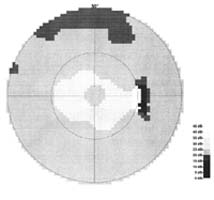

Kdybychom tak uměli spočítat množství gangliových buněk jako umíme změřit nitrooční tlak! To by se nám diagnostikoval glaukom! Na množství gangliových buněk můžeme jen usuzovat podle svazečků nervových vláken na sítnici a podle šíře neuroretinálního lemu terče zrakového nervu. Sledování změn vrstvy nervových vláken je citlivější pro včasné poznání glaukomu než sledování terče samotného. Vzhledem k variabilitě terče je obtížné stanovit jednotnou normu pro všechny lidi. Vrstva nervových vláken morfologicky je však téměř stejná u každého člověka!

Nervová vlákna

Jsme schopni sledovat vrstvu nervových vláken v každodenní praxi bez nákladných přístrojů? Ano!

Modrá šipka - ukazuje plochu na sítnici, která obsahuje nervová vlákna. Sítnice je jemně proužkovaná, světlejší, cévy "jsou jako pod závojem". Červená šipka - ukazuje místo bez nervových vláken. Sítnice je tmavší, bez proužkování. Cévy jsou ohraničeny neobvykle ostře.